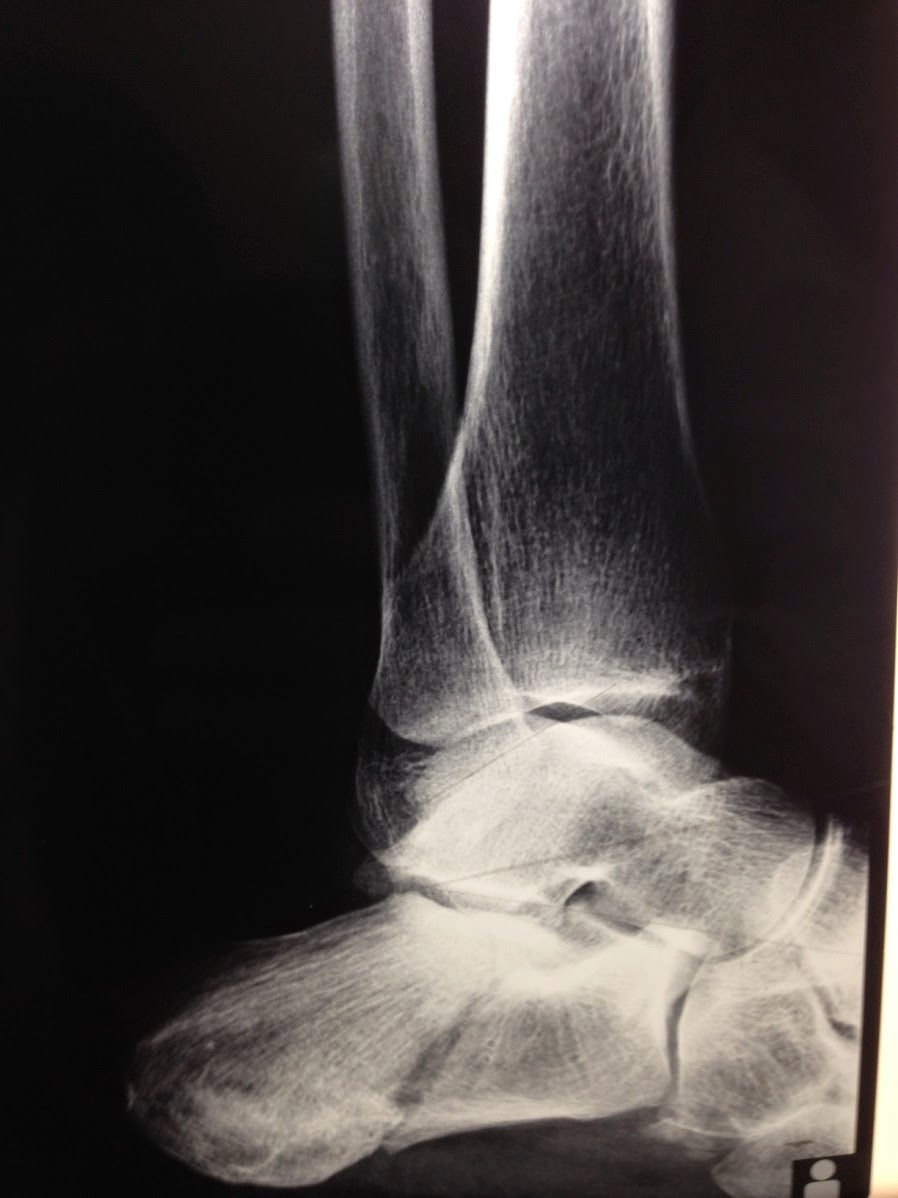

Calcaneal fractures, also known as lover's fracture and don juan fracture, are a fracture of the calcaneus or heel. Calcaneal fractures often occur after falling from what height? Calcaneal fracture, also known as lover's fracture and don juan fracture, is a fracture of the calcaneus.

Heel bone fracture,1 lover's fracture, don juan fracture. So why is it called the don juan fracture? Calcaneal fracture, also known as lover's fracture and don juan fracture, is a fracture of the the name lover's fracture is derived from the fact that a lover may jump from great heights while trying to. Don juan's fracture or also known as lover's fracture. About 2% of all fractures are calcaneal fractures.2 however, they make up 60% of fractures of the mid foot bones.2 undisplaced. It is usually caused by a fall from height when one lands on their feet. (2) burst fracture of the lumbar or thoracic the two different 'don juan fractures' share a common mechanism: The talar shelf is typically involved in subtalar or talocalcaneal tarsal coalition. Lover's fracture, also known as don juan fracture or casanova fracture is a type of calcaneal fracture. Don juan, séducteur d'une nuit see more ». Calcaneal fracture, also known as lover's fracture and don juan fracture. The don juan paraphrase has attained a terrifying (and deserved). Calcaneal fracture, also known as lover's fracture and don juan fracture, is a fracture of the calcaneus. The humorously named don juan fracture got its name from individuals who fractured their calcaneus after falling from a height (e.g. A balcony) in a hasty retreat after being caught in an affair. Calcaneal fractures, also known as lover's fracture and don juan fracture, are a fracture of the calcaneus or heel. Calcaneal fracture, also known as lover's fracture and don juan fracture, is a fracture of the calcaneal fractures are categorized into two types: